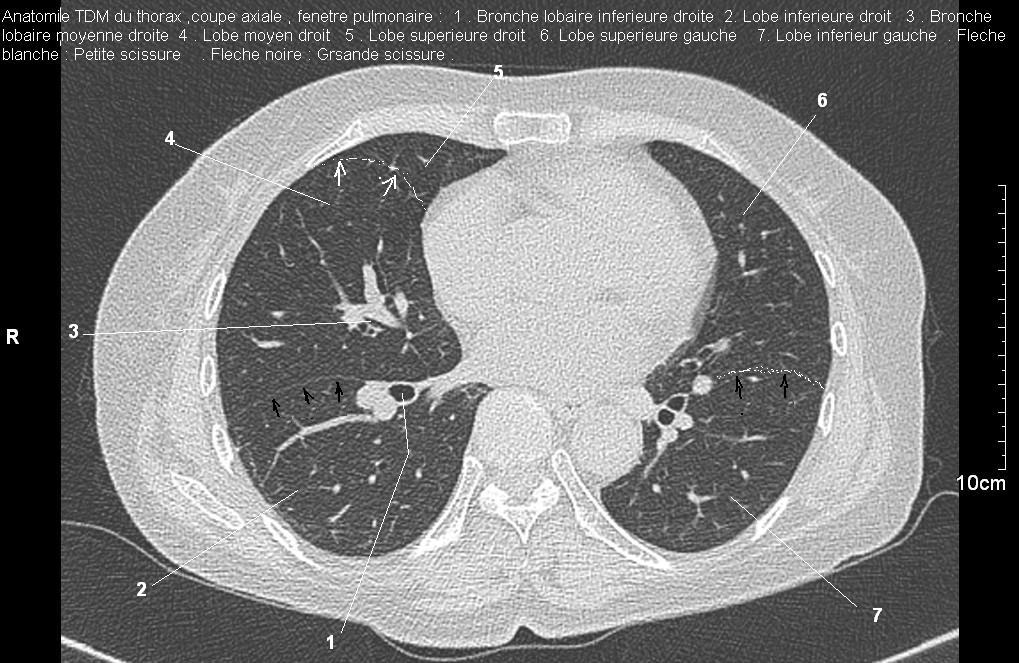

Radioanatomie pulmonaire ( image radiologie thoracique normale )- La Tomodensitometrie du  thorax ( coupes axiales fenetre pulmonaire )

Les fenetres parenchymateuses permettre d'etudier anatomie du poumon et juger sur les lesions du parenchyme pulmonaire en coupes axiales de 0,5-1cm sur le thorax .